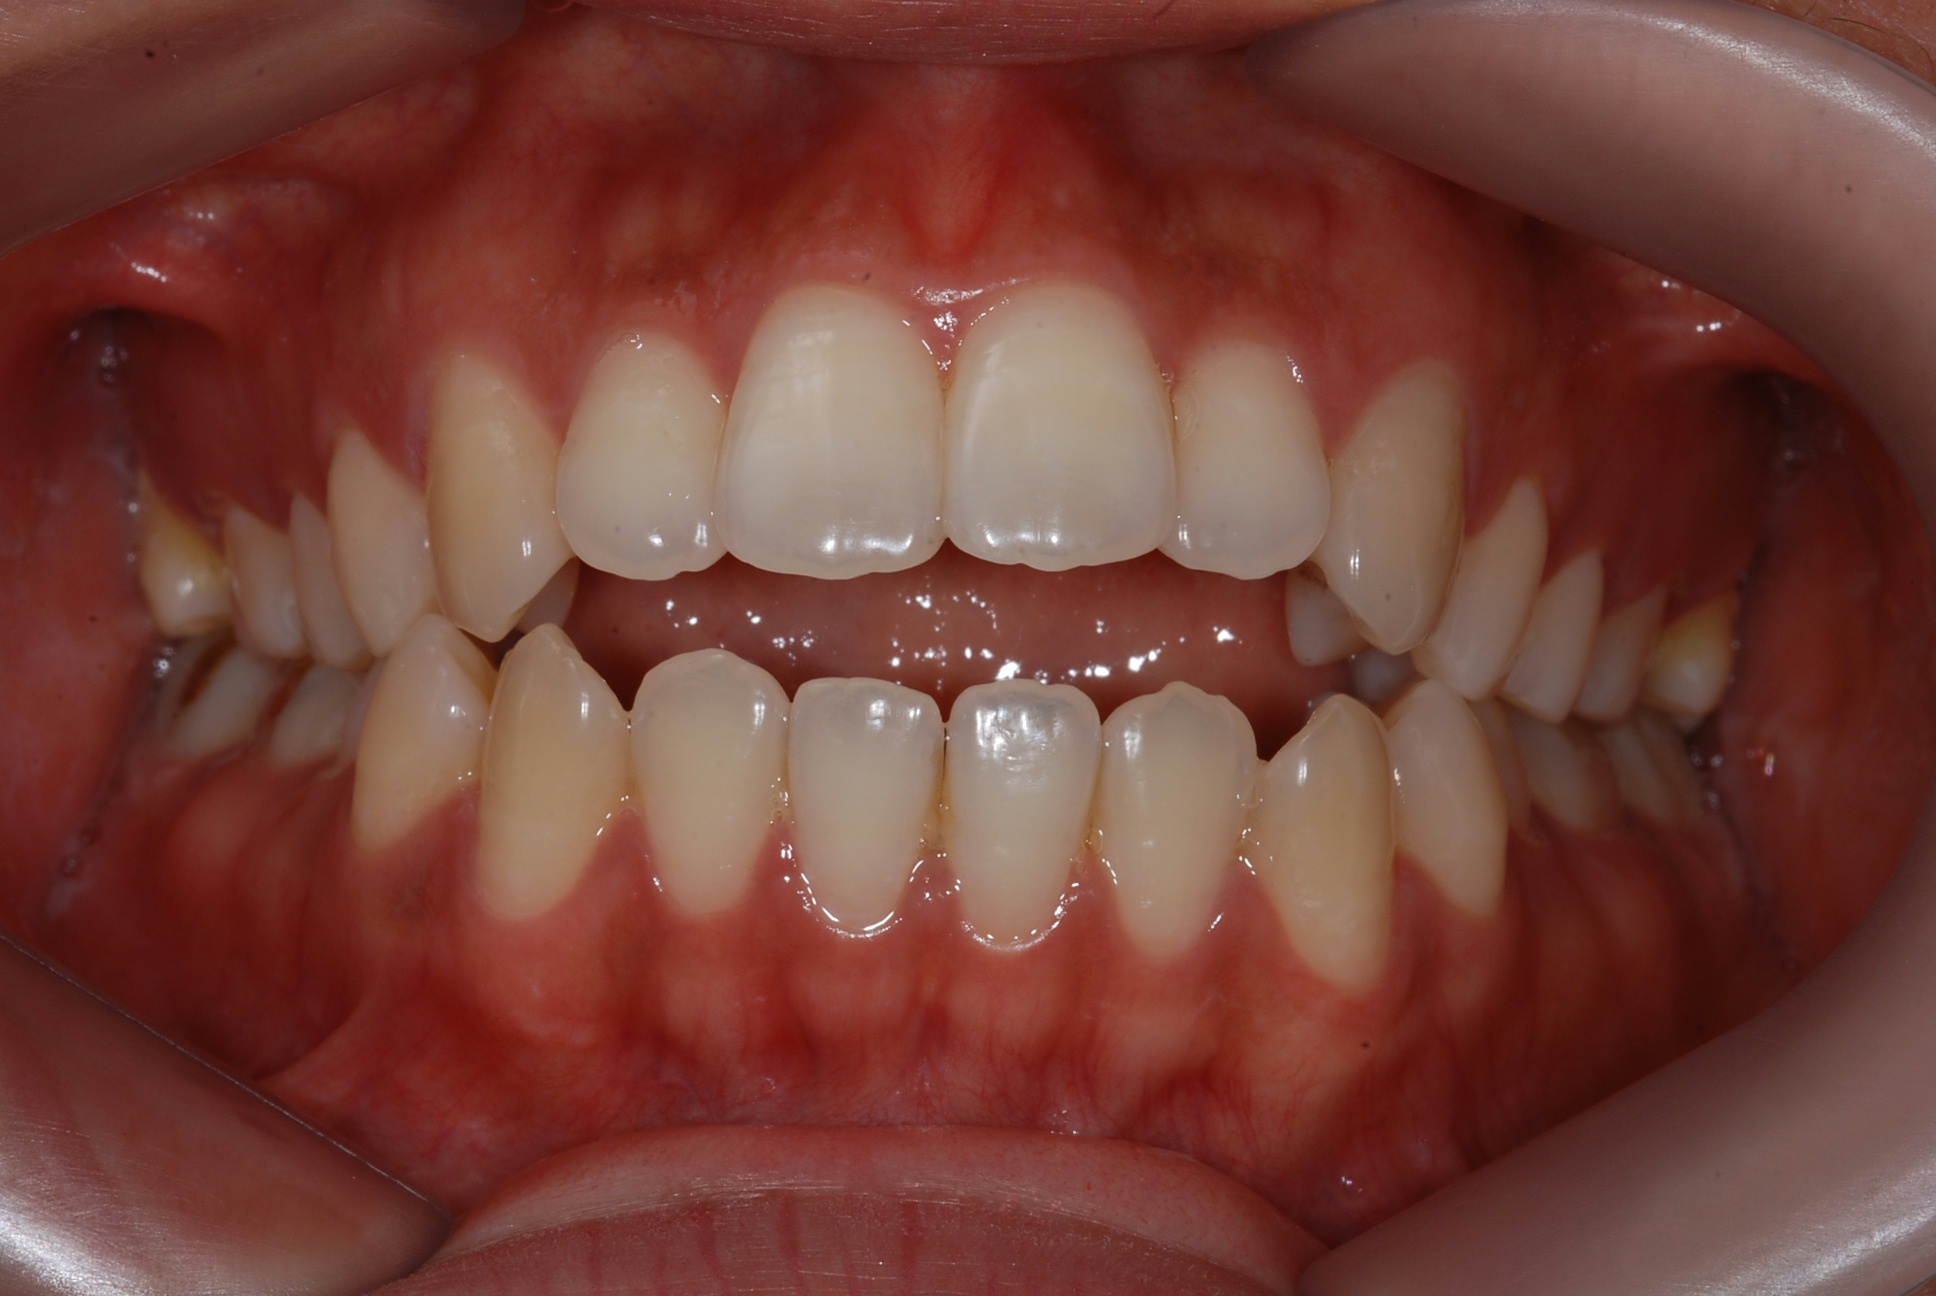

치료 후 사진입니다.